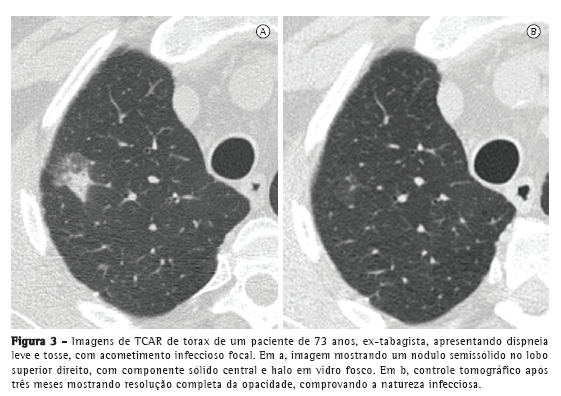

Opacidades em vidro fosco admitem múltiplos diagnósticos diferenciais, variando de doenças benignas, como fibrose focal e lesões de natureza infecciosa; opacidades pré-malignas, como hiperplasia adenomatosa atípica (HAA); até lesões malignas, como CBA e AM-CBA.(14) A atual classificação da OMS para tumores pulmonares inclui a HAA como lesão pré-maligna, precursora do CBA, com características morfológicas e moleculares próprias, cuja manifestação tomográfica mais comum é a de nódulo pulmonar com atenuação em vidro fosco.(1) Nakata et al. estudaram características tomográficas que poderiam ajudar no diagnóstico diferencial de CBA e HAA, descrevendo que HAA geralmente é < 1,0 cm e se apresenta como opacidades puramente em vidro fosco, enquanto CBA tem pelo menos 1,0 cm e pode mostrar componentes sólidos.(15) Na prática diária, o seguimento de opacidades focais em vidro fosco é crucial. A maioria das lesões benignas tende a reduzir ou desaparecer em três meses; lesões pré-malignas e malignas podem permanecer inalteradas ou aumentar (Figura 3).(16)